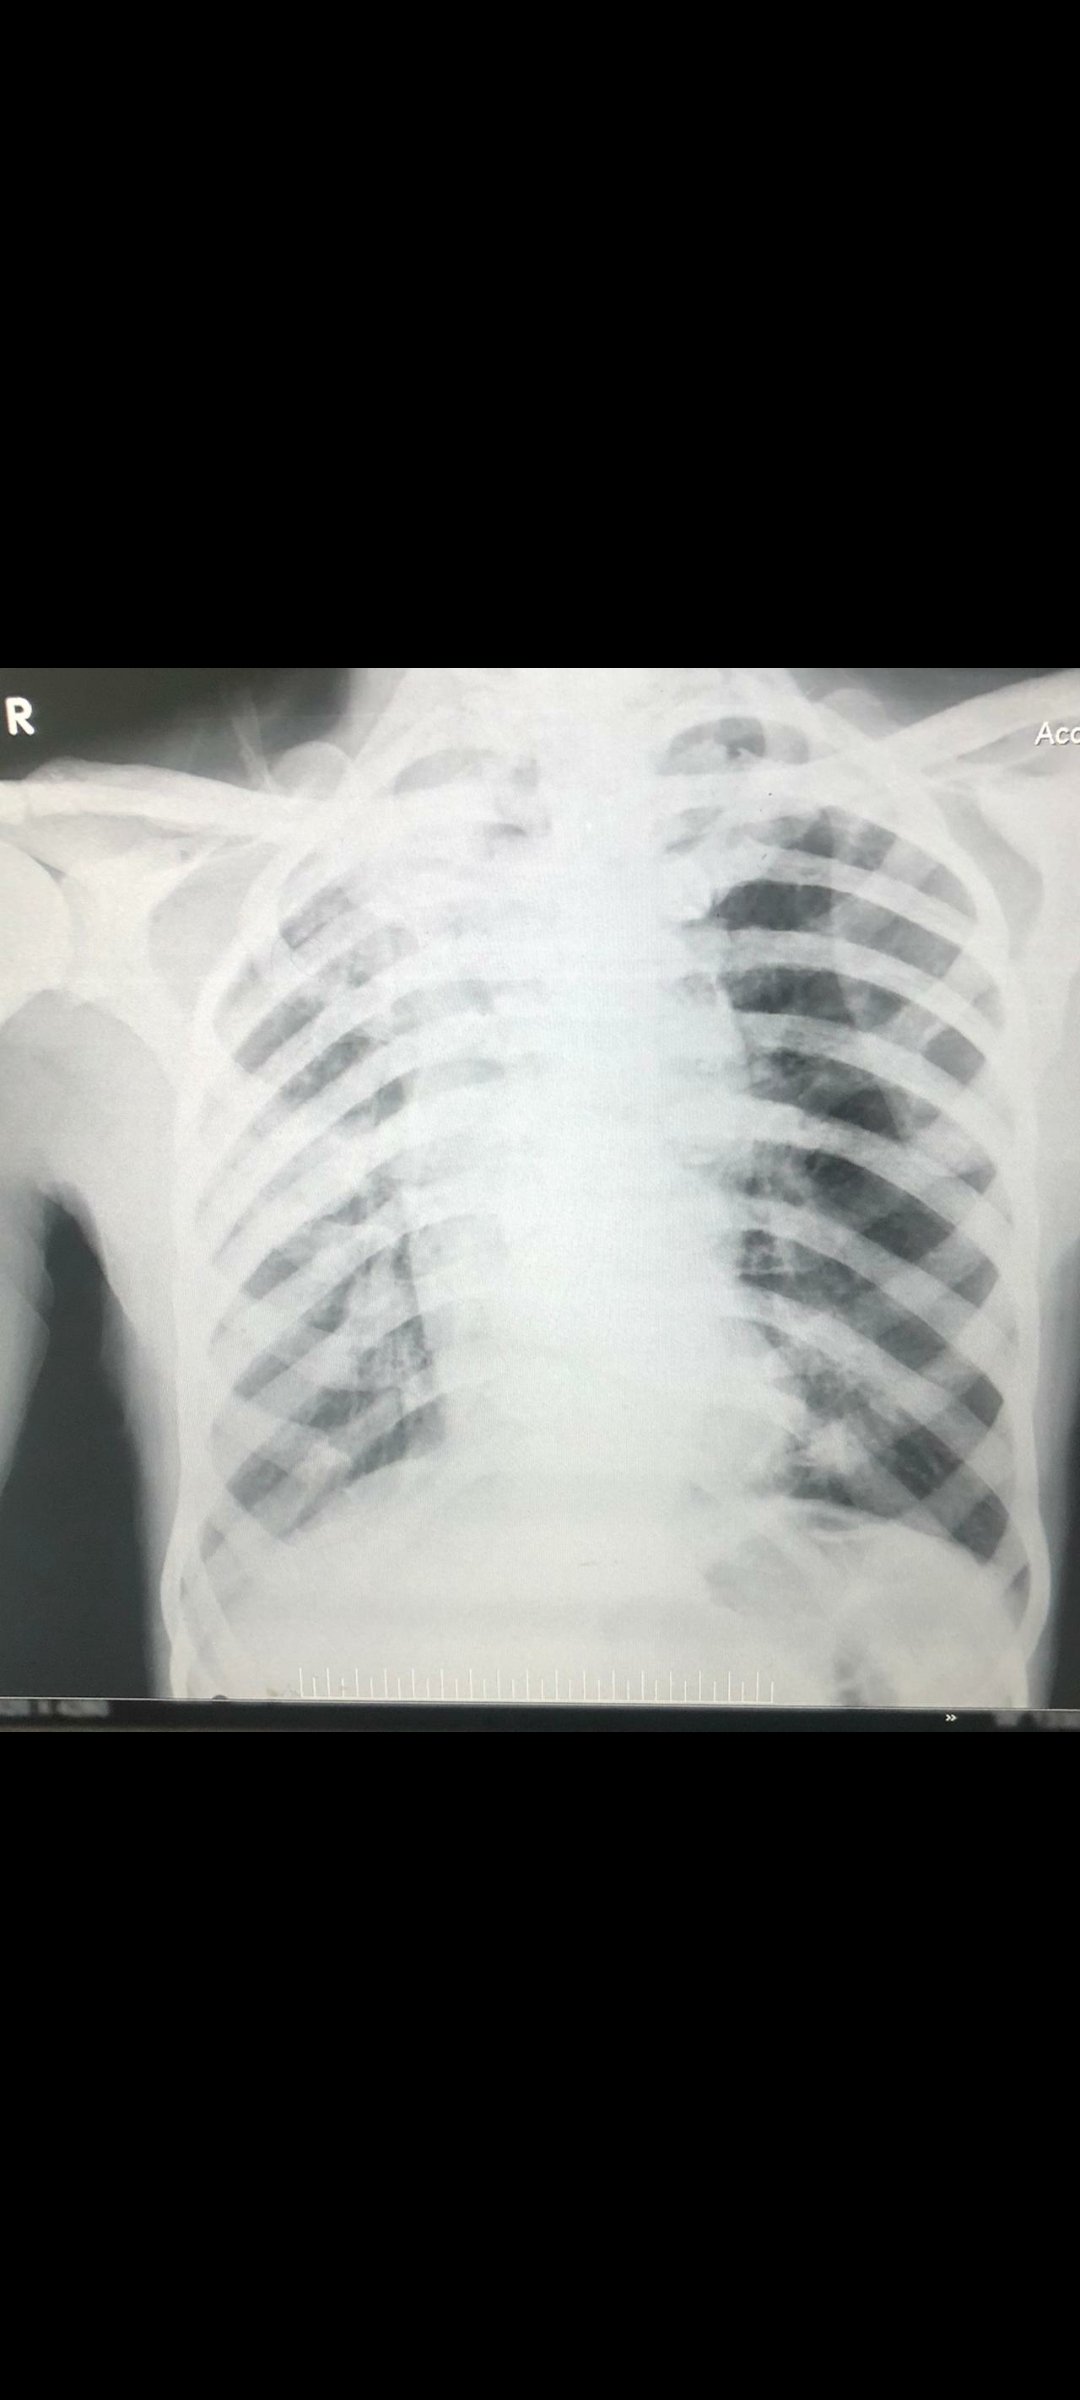

CHEST X RAY :

Multiple well defined radio opacities in B/L lung fields likely metastases

RIGHT hila is widened